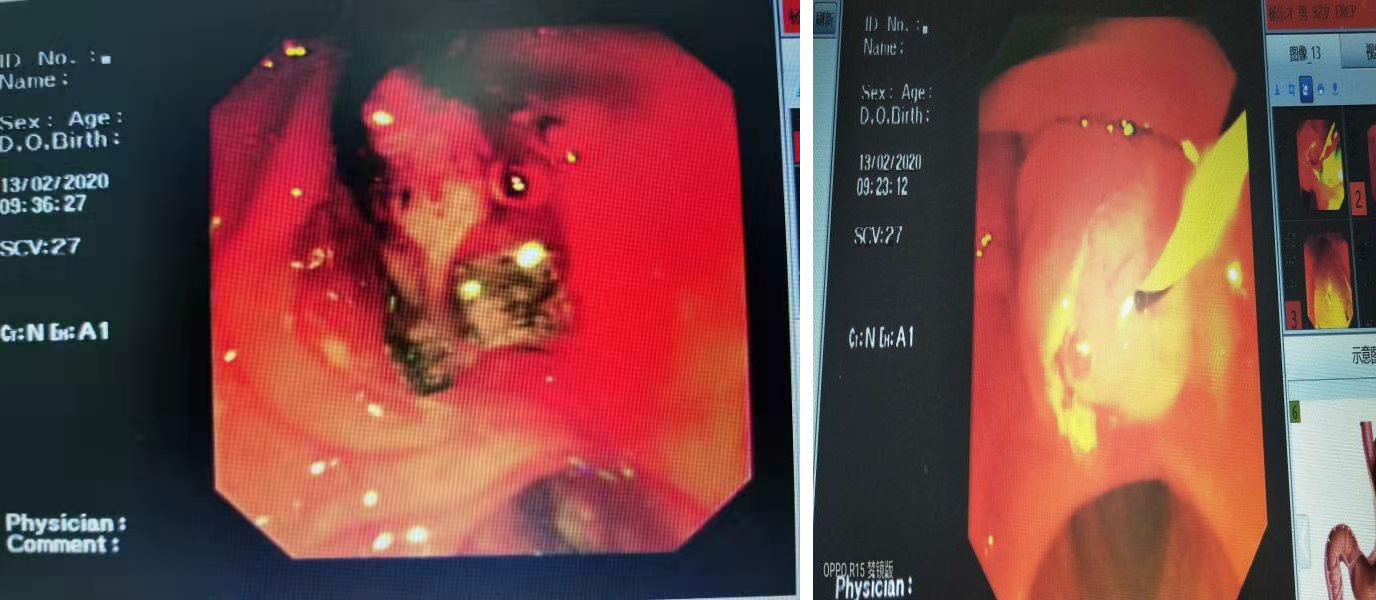

患者高齡,同時(shí)患有膽囊結(jié)石及2型糖尿病,入院時(shí)已存在寒戰(zhàn)高熱及梗阻性黃疸,如不及時(shí)處理,很可能出現(xiàn)感染性休克導(dǎo)致多臟器功能衰竭?紤]到患者平素常年臥床,心肺功能減退,外科手術(shù)風(fēng)險(xiǎn)很高,且創(chuàng)傷大,反復(fù)和家屬溝通病情,家屬決定先入該院科行ERCP。入住消化科后經(jīng)討論并充分評估病情,決定盡快行ERCP,創(chuàng)傷小,風(fēng)險(xiǎn)小,患者獲益最大。在韓新臣主任醫(yī)師的指導(dǎo)下,陳新孚副主任醫(yī)師在消化內(nèi)鏡中心護(hù)士戴文帝默契配合下用時(shí)40分鐘成功取出患者膽總管內(nèi)多枚結(jié)石,最大結(jié)石直徑10mm,另外術(shù)中發(fā)現(xiàn)膽道內(nèi)大量膿液,提示其合并化膿性膽管炎。如果確診再晚一點(diǎn),不及時(shí)行ERCP取石,患者隨時(shí)都有感染性休克可能,后果不堪設(shè)想。術(shù)后患者68歲的兒子激動的握住韓新臣主任醫(yī)師、陳新孚副主任醫(yī)師的雙手說:“您們真是妙手回春,華佗在世啊!!!”。術(shù)后患者未再出現(xiàn)發(fā)熱,也未出現(xiàn)出血穿孔及胰腺炎等并發(fā)癥;颊吆芸炜祻(fù)出院。在辦理出院的時(shí)候,老爺子像個(gè)孩子一樣開心的說:“別人感冒還要一個(gè)禮拜才能好,我得到重癥膽管結(jié)石伴感染也用了一個(gè)禮拜就康復(fù)了,徐州市第一人民醫(yī)院消化科何曉華主任,韓新臣主任,陳新孚主任,陳卓醫(yī)生還有你們消化內(nèi)鏡和消化科病房護(hù)理團(tuán)隊(duì)們,真的是無與倫比的優(yōu)秀啊!!”

膽總管結(jié)石主要癥狀是上腹痛,如合并梗阻性黃疸,很快會進(jìn)展為化膿性膽管炎,繼而出現(xiàn)感染性休克,非常兇險(xiǎn),一旦確診應(yīng)盡快行ERCP。經(jīng)內(nèi)鏡逆行性胰膽管造影術(shù)(ERCP),不用開刀,創(chuàng)傷小,并發(fā)癥較外科手術(shù)少,病人痛苦小,住院時(shí)間也大大縮短,深受患者歡迎。它主要是通過乳頭的插管,了解膽管、胰管周圍的病變。一般常見的對膽管的十二指腸乳頭的病變,或者胰腺、胰腺結(jié)石,胰腺腫瘤或者胰管狹窄疾病的診斷和治療。適應(yīng)證主要是1.膽管結(jié)石、腫瘤、炎癥、寄生蟲;2、不明原因的阻塞性黃疸;3、復(fù)發(fā)胰腺炎、膽源性胰腺炎、慢性胰腺炎、胰腺腫瘤;4、膽胰先天性病變、膽胰管引流異常;5、膽胰手術(shù)、外傷后的膽胰、胰瘺、狹窄;6、膽囊切除、膽管手術(shù)后癥狀復(fù)發(fā)、奧狄氏括約肌功能紊亂;7、十二指腸乳頭壺腹部腫瘤;8、某些肝臟疾病。徐州市第一人民一院消化科已開展ERCP近20年,團(tuán)隊(duì)是專業(yè)的,是優(yōu)秀的!